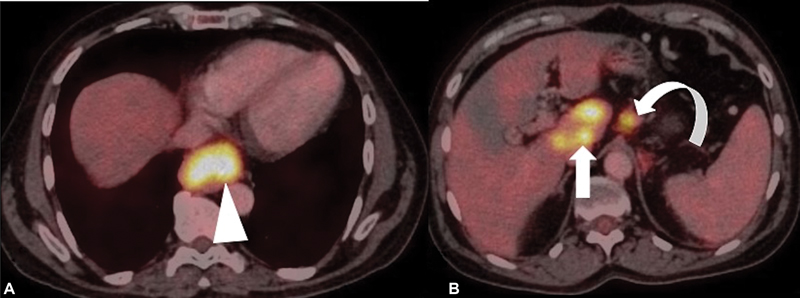

Following intravenous injection of 18F-FDG-PET-CT images are acquired from skull base to mid-thigh. Both oral and intravenous contrast is used for the acquisition of CT images. The predominant role of FDG-PET/CT is to detect distant metastases including metastasis to bones and distant nodal metastasis when no metastasis is detected on CECT scan.[16] PET-CT is the modality of choice to diagnose occult metastasis to various organs that thus help in avoiding futile surgeries.[30] [31] [32] Besides, PET-CT is also useful to detect second primary tumor and studies have indicated that FDG-PET/CT is superior to conventional anatomical imaging to evaluate synchronous tumors (especially head and neck cancers and colon neoplasm) during primary staging of esophageal SCC.[33] PET/CT also plays an important role in radiation therapy treatment planning of EC.[34] [35] PET-CT-based intensity-modulated radiation therapy offers several advantages that includes (1) dose escalation to target (tumor), (2) minimizes dose delivery to normal tissue, (3) decrease acute toxicity, (4) lessens long-term toxicity by optimizing treatment delivery to target tissue, thereby achieving better therapy outcome. [Fig. 4 (A] and [B)] shows EC staging on FDG-PET/CT.

| Figure 4:(A and B) Staging of esophageal cancer on fluorodeoxyglucose-positron emission tomography/computed tomography (FDG-PET/CT) images reveals moderately FDG-avid primary esophageal mass lesion (arrowhead) with extensive FDG-avid metastatic abdominal nodes (curved arrow) and multifocal hypermetabolic hepatic (metastatic) lesions (arrow) implying M1